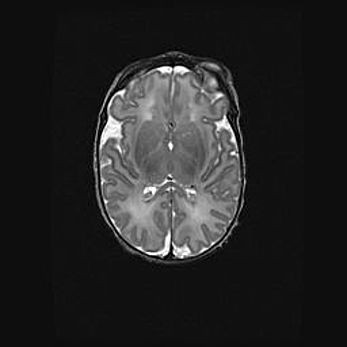

Сообщающаяся гидроцефалия. Кистозная энцефаломаляция головного мозга.

Возраст: 3 месяца 4 дня

Вес: 3100 г

Пол: женский

Окружность головы: 34 см

Срок гестации: 31 неделя

Кистозная энцефаломаляция головного мозга - одна из форм поражения головного мозга в детском возрасте. Характеризуется возникновением множественных и распространённых кист в коре, белом веществе и подкорковых образованиях головного мозга у плодов, новорождённых и детей раннего возраста. Развитие кистозной энцефаломаляции связано с внутриутробной асфиксией и гипотонией, родовой травмой, тромбозом синусов, пороками развития сосудов, инфекциями, сепсисом и другими причинами. Наиболее значимые инфекционные агенты: вирусы простого герпеса, цитомегалии, краснухи, токсоплазмы, энтеробактерии, золотистый стафилококк и другие.